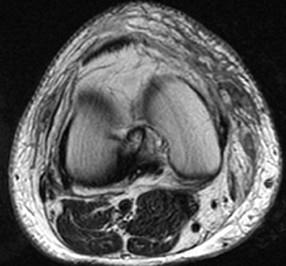

问题 男,39岁,右膝关节有外伤史,感膝关节疼痛,活动后加剧,请结合所提供的图像,选择最佳选项 ( )

选项 A、胫骨骨折 B、后十字韧带撕裂 C、前十字韧带撕裂 D、内侧半月板撕裂 E、未见异常

答案 B